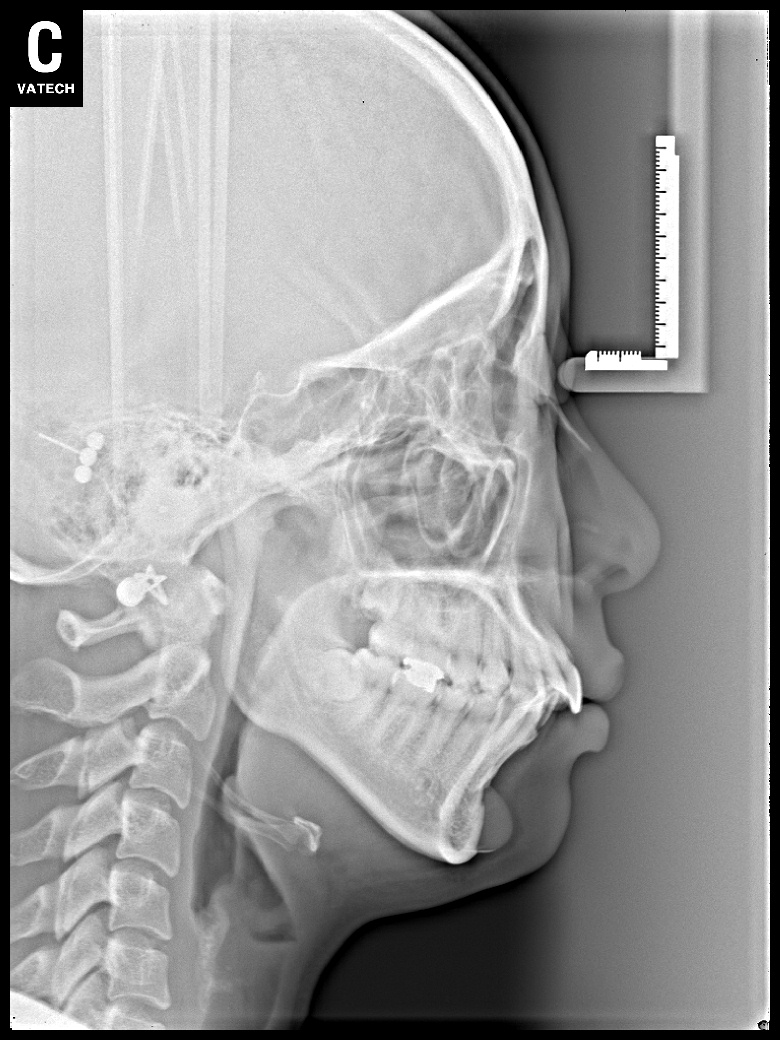

치료 전 사진입니다.